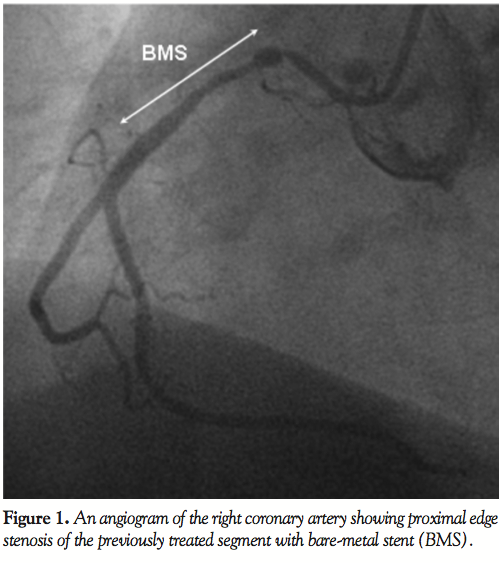

Case description. A 76-year-old man with previous history of stent implantation to his proximal right coronary artery was admitted to our hospital because of unstable angina pectoris. Although previous angiography as well as coronary intervention could be performed without any complications, anaphylactoid reaction with hypotension was reported 1 month prior to admission when he underwent contrast-enhanced computed tomography. Coronary angiography was carefully performed under prophylactic steroid administration and revealed proximal edge stenosis of the initially stented right coronary artery (Figure 1). During angiography, he became hypotensive (systolic blood pressure < 50 mmHg) with skin rash requiring noradrenalin administration, despite the use of prophylactic corticosteroid. He was medically treated with intravenous nitrate and heparin in addition to oral antiplatelet therapy. Despite the intensive medial treatment, his angina could not be managed. Therefore, PCI without using iodinated contrast media was planned and performed.